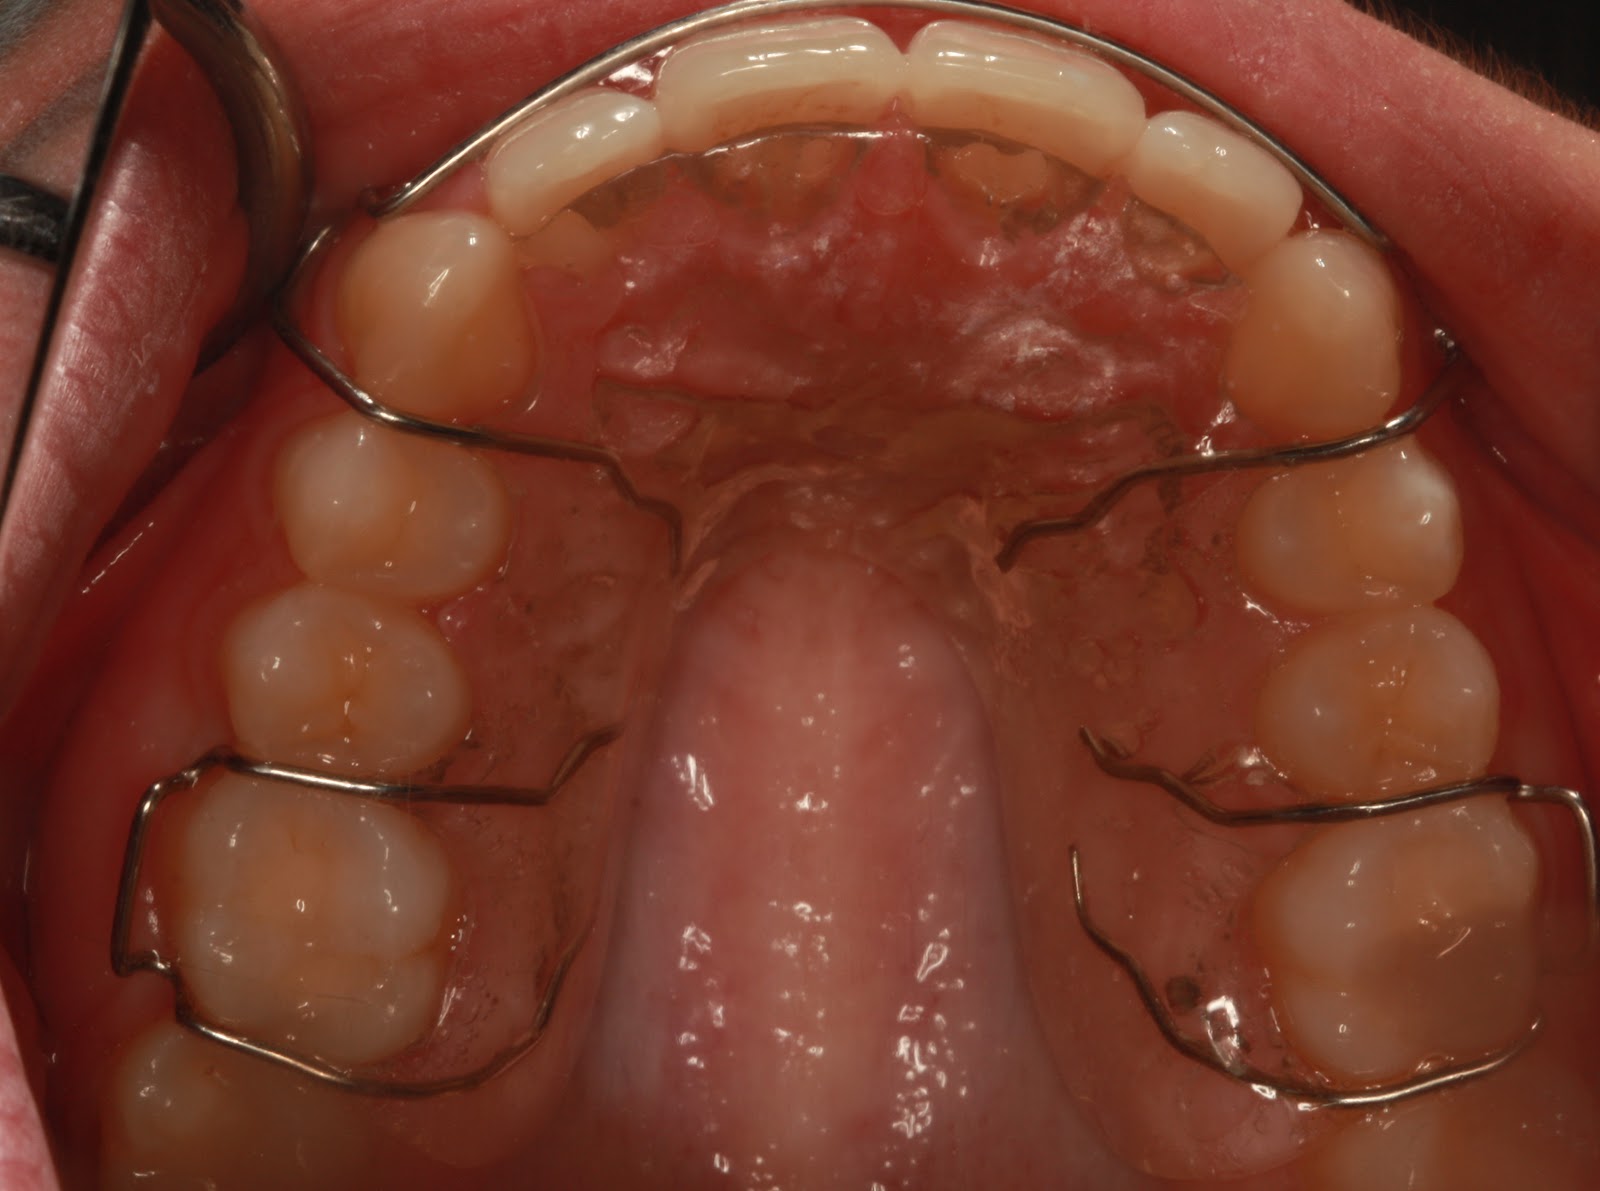

"Πάρε αυτό το μασελάκι

Θα το φοράς στην αρχή για 6 μήνες ή ένα χρόνο και στη συνέχεια θα πρέπει να το φοράς κάποιες μέρες της εβδομάδας όταν κοιμάσαι για να διατηρηθεί αυτό το χαμόγελο"

Το μασελάκι που σας έδωσε ο ορθοδοντικός λέγεται μηχάνημα σταθεροποίησης της ορθοδοντικής θεραπείας (ή retainer στην αγγλική επιστημονική ορολογία) και σκοπό έχει να διατηρήσει το αποτέλεσμα της ορθοδοντικής θεραπείας,μια και τα δόντια έχουν την τάση να κουνιούνται,με αποτέλεσμα να υπάρχει πιθανότητα να στραβώσουν.Μετά την αφαίρεση των συρμάτων πρέπει να το φοράνε οι ασθενείς συνέχεια για κάποιο διάστημα, που εξαρτάται από τη φύση και την έκταση του προβλήματος τους,και στη συνέχεια να το φοράνε δύο με τρεις φορές την εβδομάδα για πάντα ή να κάνουν μια μόνιμη ακινητοποίηση δοντιών.

Παρακάτω θα δούμε πραγματικά παραδείγματα ασθενών με μηχάνημα σταθεροποίησης αλλά και με ακινητοποίηση.

Ακινητοποίηση κάτω δοντιών Ακινητοποίηση άνω δοντιών

Συνήθως στα κάτω γίνεται ακινητοποίηση και στα άνω μηχάνημα σταθεροποίησης χωρίς όμως αυτό να είναι κανόνας.Όλα γίνονται πάντα σε συνεννόηση με τον ασθενή και τα θέλω του.